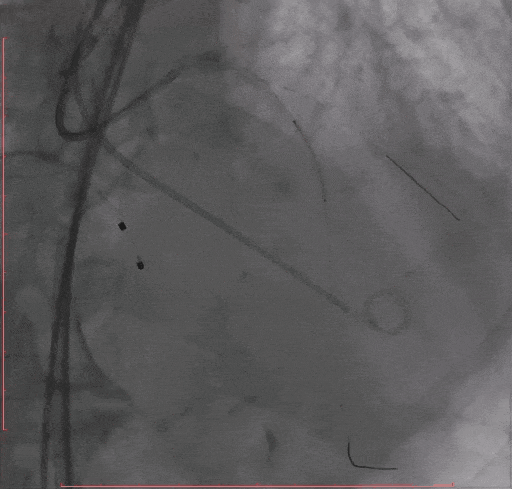

Step 2.冠脉造影

Step 3.导丝跨主动脉瓣后,干预冠脉病变,球囊无法通过LAD病变,予以旋磨

Step 4 旋磨后予以前降支支架植入

Step 5 左主干植入支架 回旋支开口予以切割+药物球囊